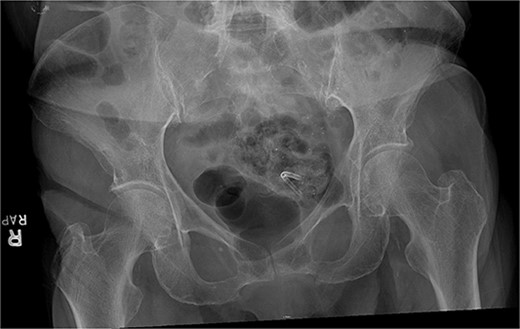

A 79-year-old female presented to the emergency department with progressively worsening abdominal pain, nausea, vomiting, intermittent chills, and non-bloody mucoid bowel movements. Her medical history was significant for a previous cardiovascular accident, dementia, emphysema, hypertension, gastroesophageal reflux disease, diverticulosis, type 2 diabetes mellitus, and hypothyroidism. The patient’s surgical history included a recent endoscopic retrograde cholangiopancreatography with biliary sphincterotomy, debris removal, and stent placement for acute cholangitis with choledocholithiasis. At that time, an 8.5 Fr × 7 cm straight plastic biliary stent was inserted in the common bile duct followed by a robotic-assisted laparoscopic cholecystectomy during the same admission. Two weeks later, an outpatient esophagogastroduodenoscopy (EGD) was performed for the removal of the biliary stent; however, it was not visualized protruding from the major duodenal papilla. Abdominal and pelvic radiographs revealed the migrated stent overlying the pelvis within the region of the sigmoid colon (Fig. 1). Given her stable clinical presentation, gastroenterology decided to wait for the stent to spontaneously pass.